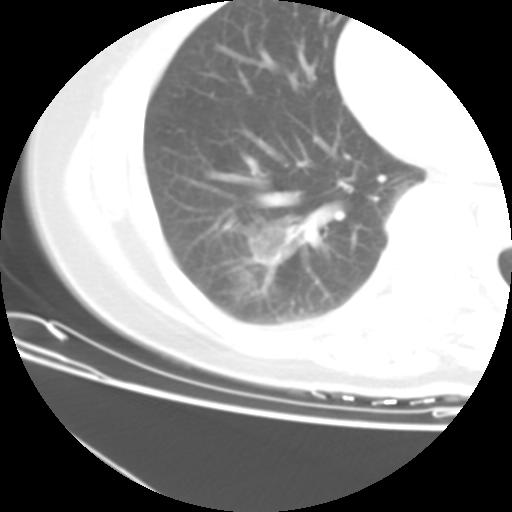

右肺下叶类癌

女 46岁,咳嗽咳血10月

【linyiming】右肺下叶见类圆形软组织影,边缘欠规整,略分叶状。考虑炎症假瘤可能?

未排除周围型肺癌。建议CT增强。

【aosangwa】肺癌的主要特征是:毛刺征、分叶征及胸膜凹陷征,此病例位于右肺下叶距胸膜很近,但没有胸膜凹陷征,其周围像示渗出性病变,病灶在两窗上没有大小没有发生大小改变。

考虑其良性肿瘤,炎性假瘤可能性大,其主要鉴别是:结核球、周围型肺癌、血管瘤

病理诊断类癌(周围型)。